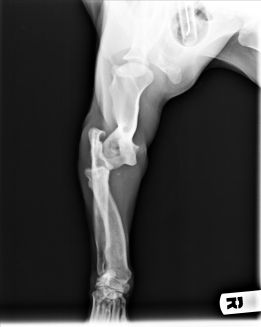

Enseguida nos hicimos cargo de él. Tras pasar una primera revisión veterinaria, decidimos trasladarlo a Madrid a una casa de acogida para tener una segunda opinión de un traumatólogo de nuestra confianza. El resultado fue el diagnóstico de luxación de codo en la pata delantera, y de fractura de huesos con luxación en la pata trasera. El problema es que estas lesiones tenían una antigüedad de unas 5 semanas, por lo que ya se había empezado a formar fibrosis y callo. Con todo ello se decidió dejar que la fractura siguiese su consolidación, y operar la luxación de codo, para intentar que recuperase completamente su funcionalidad.

Como se puede ver en las radiografías, con dos cirugías sobre la articulación, se consiguió la perfecta recolocación.